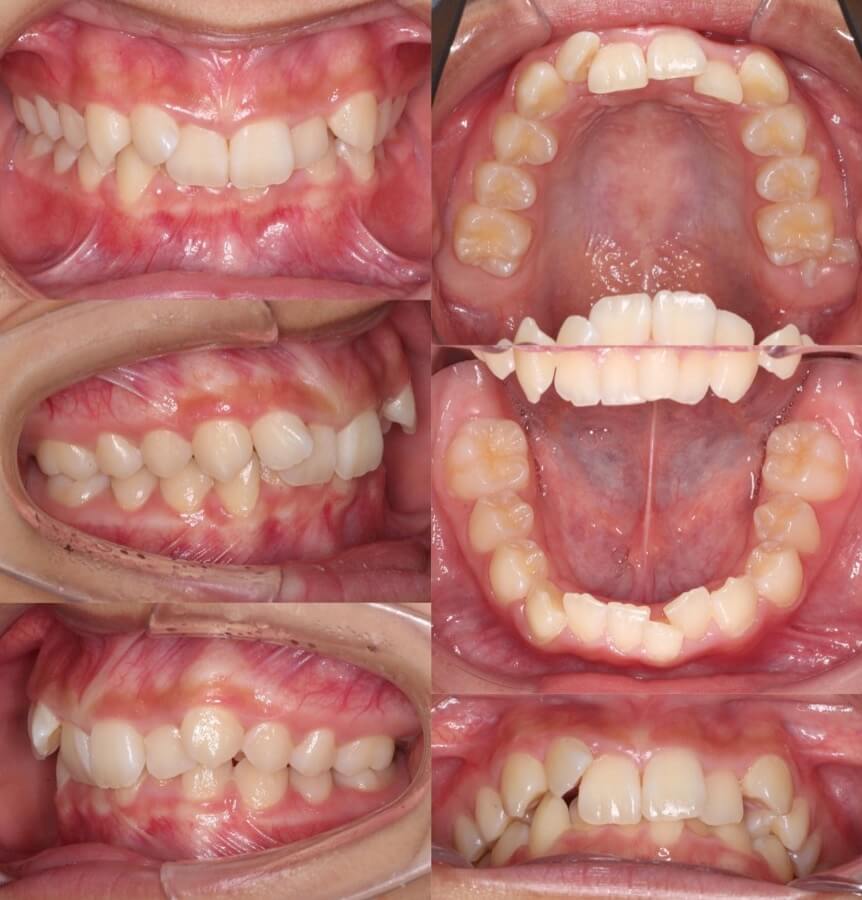

20代女性・唇側矯正装置・2本抜歯

重度の過蓋咬合であったため、唇側ワイヤー矯正装置とアンカースクリューにより、先に上の前歯の圧下(歯茎方向への移動)を行なった後に、ゆっくりと抜歯空隙を閉鎖しました。このように過蓋咬合では前歯に植立するアンカースクリューがあった方が治療が効率的に進みます。

<症例概要>

主訴:前歯の突出と噛み合わせ

年齢・性別:20代女性

住まい:東京都練馬区

症状:過蓋咬合・上顎前突

治療方針:上顎前歯の圧下・抜歯空隙の閉鎖

治療装置:唇側矯正装置

固定装置:歯科矯正用アンカースクリュー(上唇側x2)

抜歯:上左右第一小臼歯(計2本)

治療期間:2年6か月

リテーナー:下フィックスタイプ+上下プレートタイプ

治療費用:968,000(税込)

代表的副作用:痛み・治療後の後戻り・歯根吸収・歯髄壊死・歯肉退縮

▶︎その他の副作用

20代女性・マウスピース型装置

過蓋咬合の改善は見た目の変化は少ないのですが、口の中の歯並びの変化は大きいです。下の歯並びが見えるようになり正しいかみ合わせになりました。

主訴:前歯のかみ合わせが悪い

年齢・性別:大学生女性

住まい:千葉県佐倉市

症状:過蓋咬合・右5番シザーズバイト・下顎叢生

治療方針:下顎前歯唇側傾斜による圧下

治療装置:マウスピース型矯正装置(アライナー装置)

アライナー枚数:43+27

治療期間:1年4か月

リテーナー:上下クリアタイプ

治療費用:990,000(税込)

主に下の歯並びを前方に倒しながら歯茎方向に沈め(圧下)させ、過蓋咬合を改善していきます。